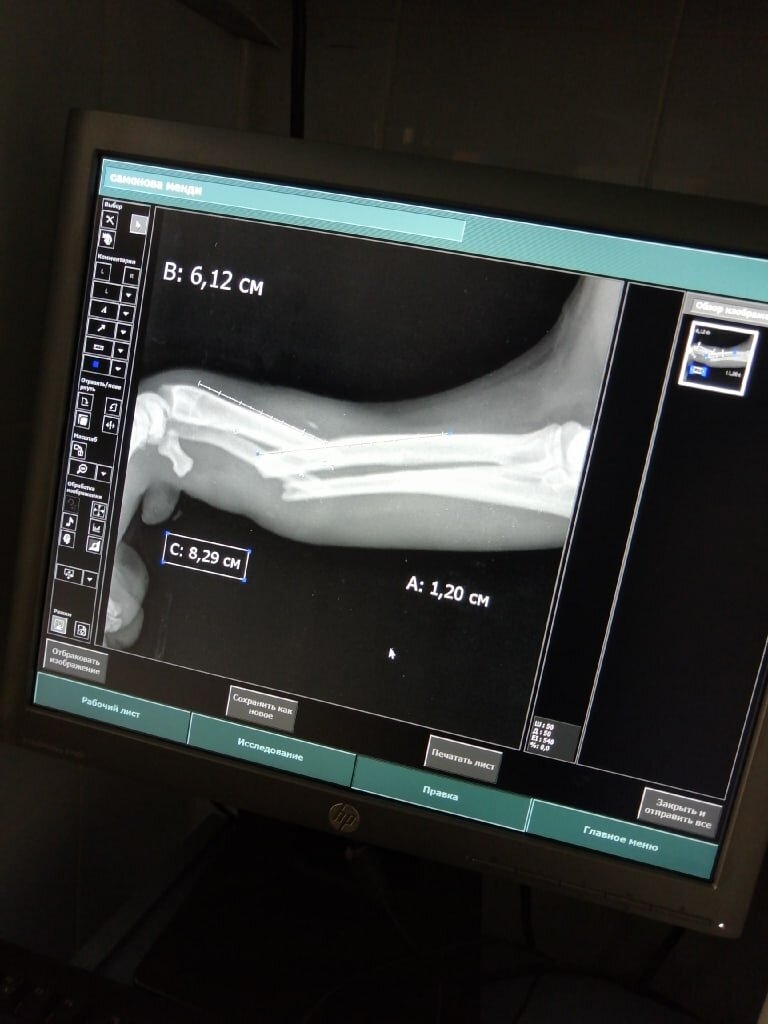

Женщина, которая её подкармливала, связалась со мной и попросила свозить собаку в клинику, так как у неё была травмирована лапа. Рентген в клинике показал перелом двух костей передней лапы, что, скорее всего, явялеется результатом ДТП. Через несколько дней повезли её на операцию в Никольский, где ей поставили пластину. Одну из костей так и не получилось соединить, но опора при ходьбе будет именно

Женщина, которая её подкармливала, связалась со мной и попросила свозить собаку в клинику, так как у неё была травмирована лапа. Рентген в клинике показал перелом двух костей передней лапы, что, скорее всего, явялеется результатом ДТП. Через несколько дней повезли её на операцию в Никольский, где ей поставили пластину. Одну из костей так и не получилось соединить, но опора при ходьбе будет именно на ту кость, на которую поставили пластину. Менди пока не встаёт на лапу, хотя активно бегает на трёх. Уже повторно делали рентген и получили новый курс лечения от врача. Надо ждать, надо принимать лекарства и смотреть, как будет дальше.